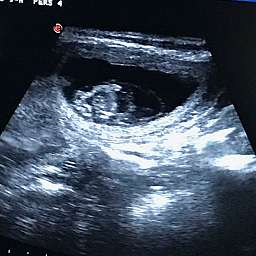

12.6.2018, 30.Tag: Um 11.00Uhr startete unser großer Moment: Adeles Wunder wurde von unserer Tierärztin geschallt.

Wir sind überglücklich Euch mitteilen zu dürfen, daß Adele tragend ist. Beim Ultraschall sahen wir völlig überwältigt 4 - 5 kleine Fruchthüllen mit pochenden Herzen darin.